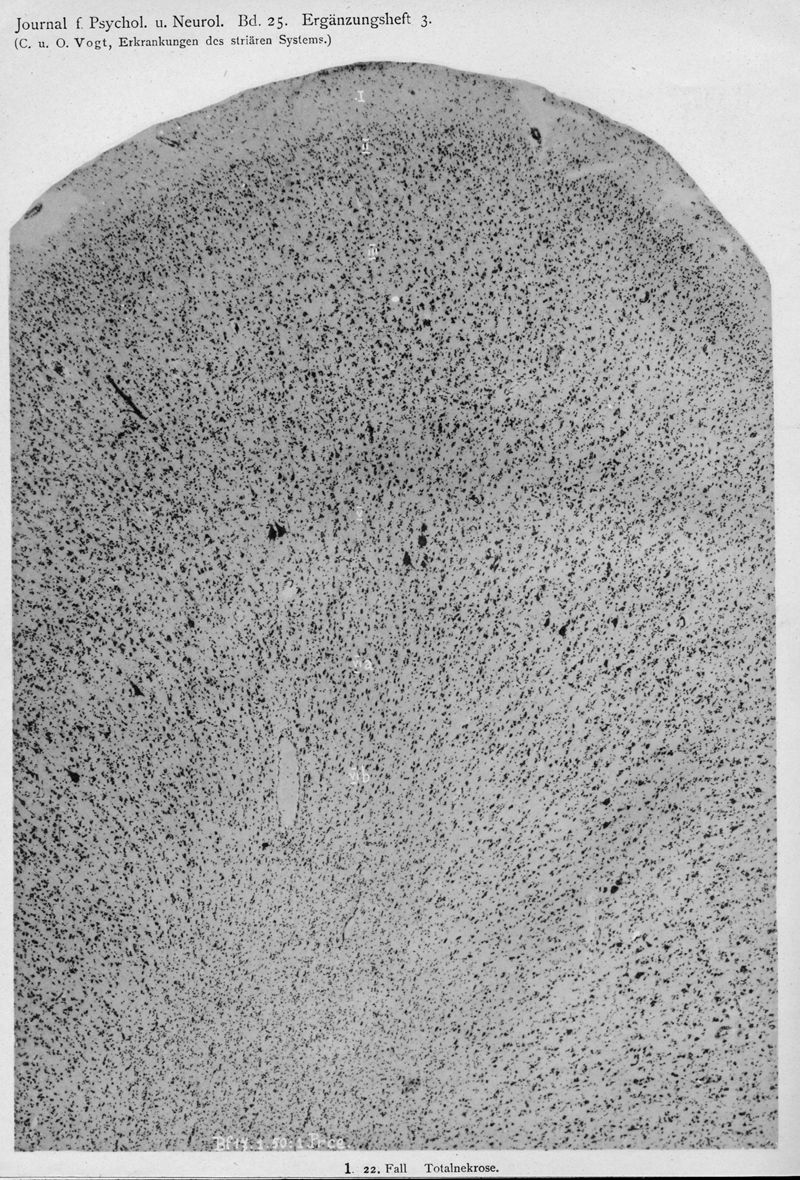

VOGT, Cécile / VOGT, O.

In : Journal für Psychologie und Neurologie,

1920, Vol. 25, pp. 627-846